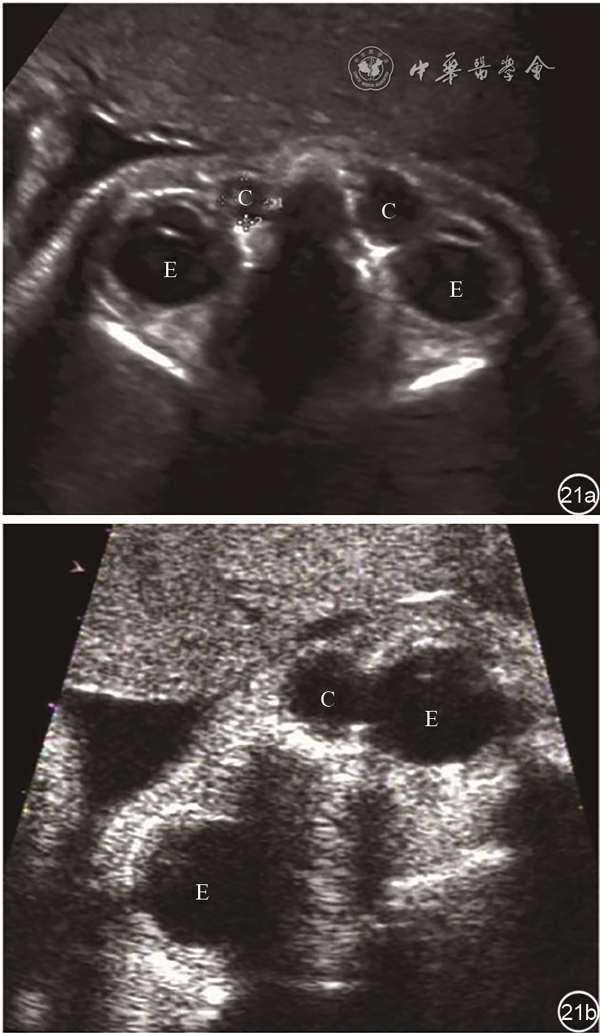

双眼球水平横切面上发现眼眶前内侧囊性暗区应考虑本异常可能(图21),部分病例可在胎儿期随着鼻泪管的管化而消失。一项对75例泪囊膨出病例的研究显示,可随访到的出生胎儿中,90.6%(58/64)的囊肿在宫内自行缓解或消失,出生后确诊的病例均未经手术治疗自行缓解35。泪囊膨出需要与颜面部其他包块如血管瘤、淋巴管瘤、横纹肌瘤相鉴别,但很容易通过回声特点、大小、位置、彩色多普勒成像等做出鉴别。

图21 单侧和双侧泪囊膨出胎儿产前超声图像。孕30周胎儿双眼球水平横切面双眼球(图a)及一侧眼球(图b)内侧囊性暗区

注:C为泪囊膨出囊性暗区;E为眼球